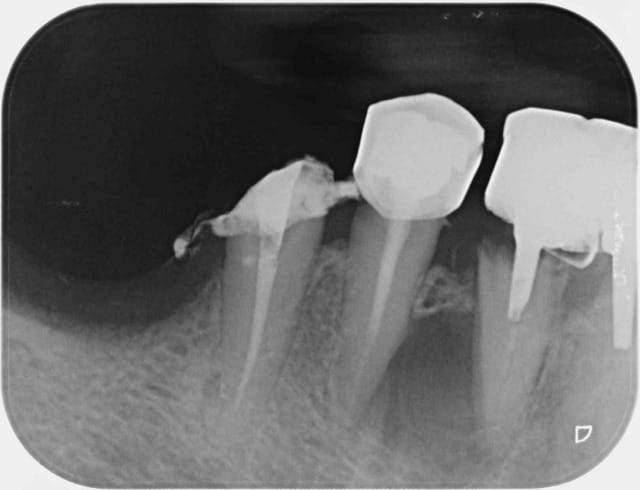

Sur un nouveau patient. Il fait une drôle de tête ce bridge. ;-)

> Sur un nouveau patient. Il fait une drôle de tête ce bridge. ;-)

Le pilier mésial aussi!!!